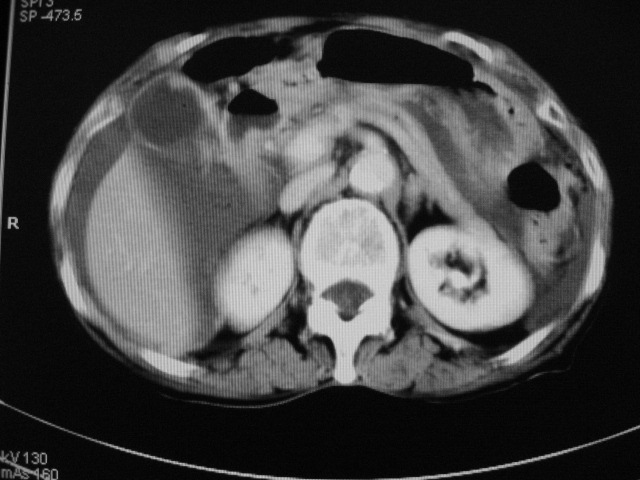

以下是引用zjzjr在2007-9-20 19:15:00的发言:[br]慢性胆囊炎伴炎性息肉可能性大.腹水.

以下是引用默契在2007-9-20 17:29:00的发言:[br][br] [br] 考虑:1、胆囊占位性病变(以癌可能性大);[br] 2、中量腹水。 [br] [br]

以下是引用快乐男生在2007-9-20 15:32:00的发言:[br]图像质量不好:[br]胆囊增大,囊壁增厚,[br]可见结节突出囊腔内,[br]增强后与囊壁相仿.[br]考虑多为胆囊慢性炎症伴有胆囊体部的息肉